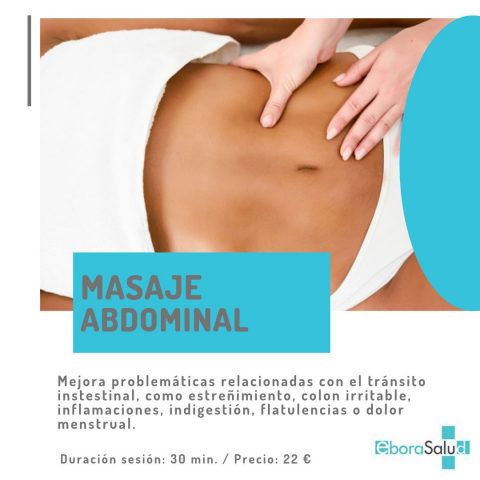

En Eborasalud Clínica Médica innovamos para mejorar la calidad de vida de nuestros pacientes. Por ello, ponemos en marcha una Unidad de Bienestar y Fisioterapia con una serie de tratamientos fisioterapéuticos destinados a mejorar y ser coadyuvantes de nuestros servicios médicos. MASAJE FACIAL CRANEAL Probablemente piensas en ir al fisioterapeuta para tratar la musculatura de […]